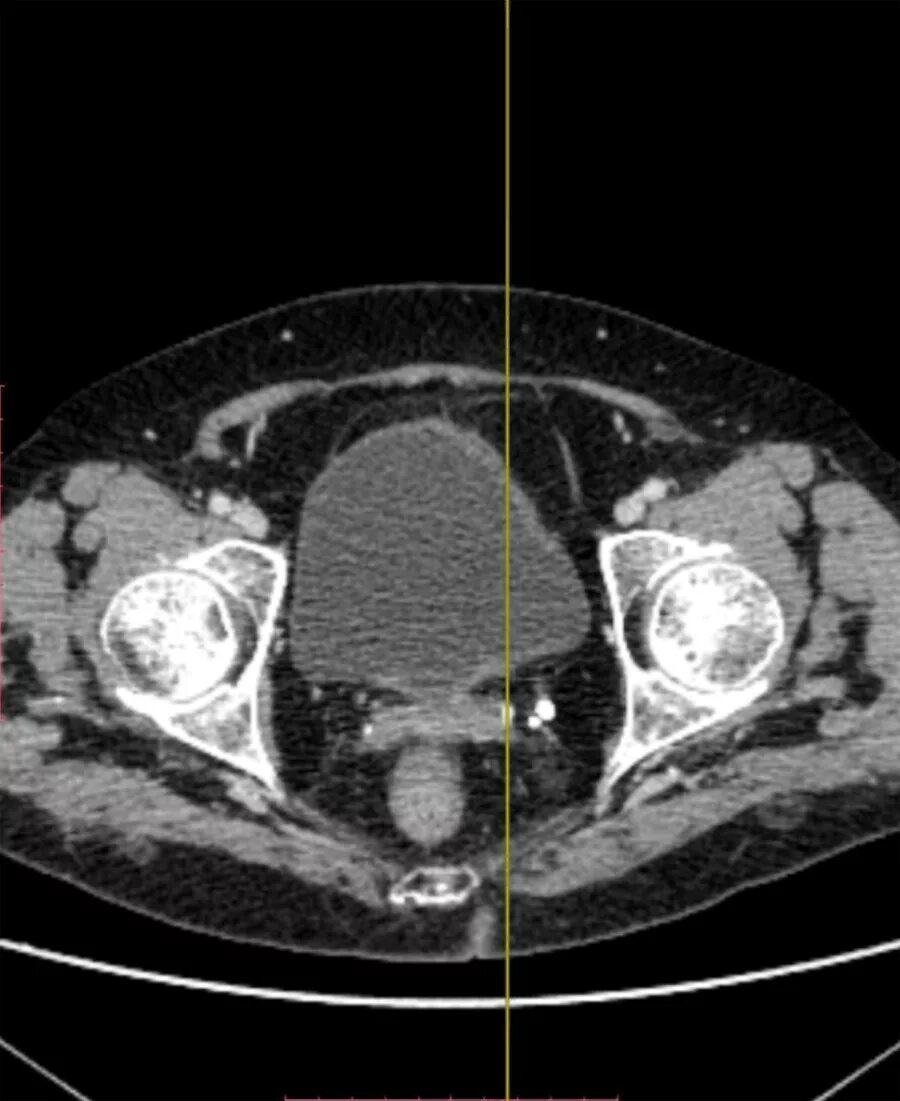

Инволютивные изменения яичников